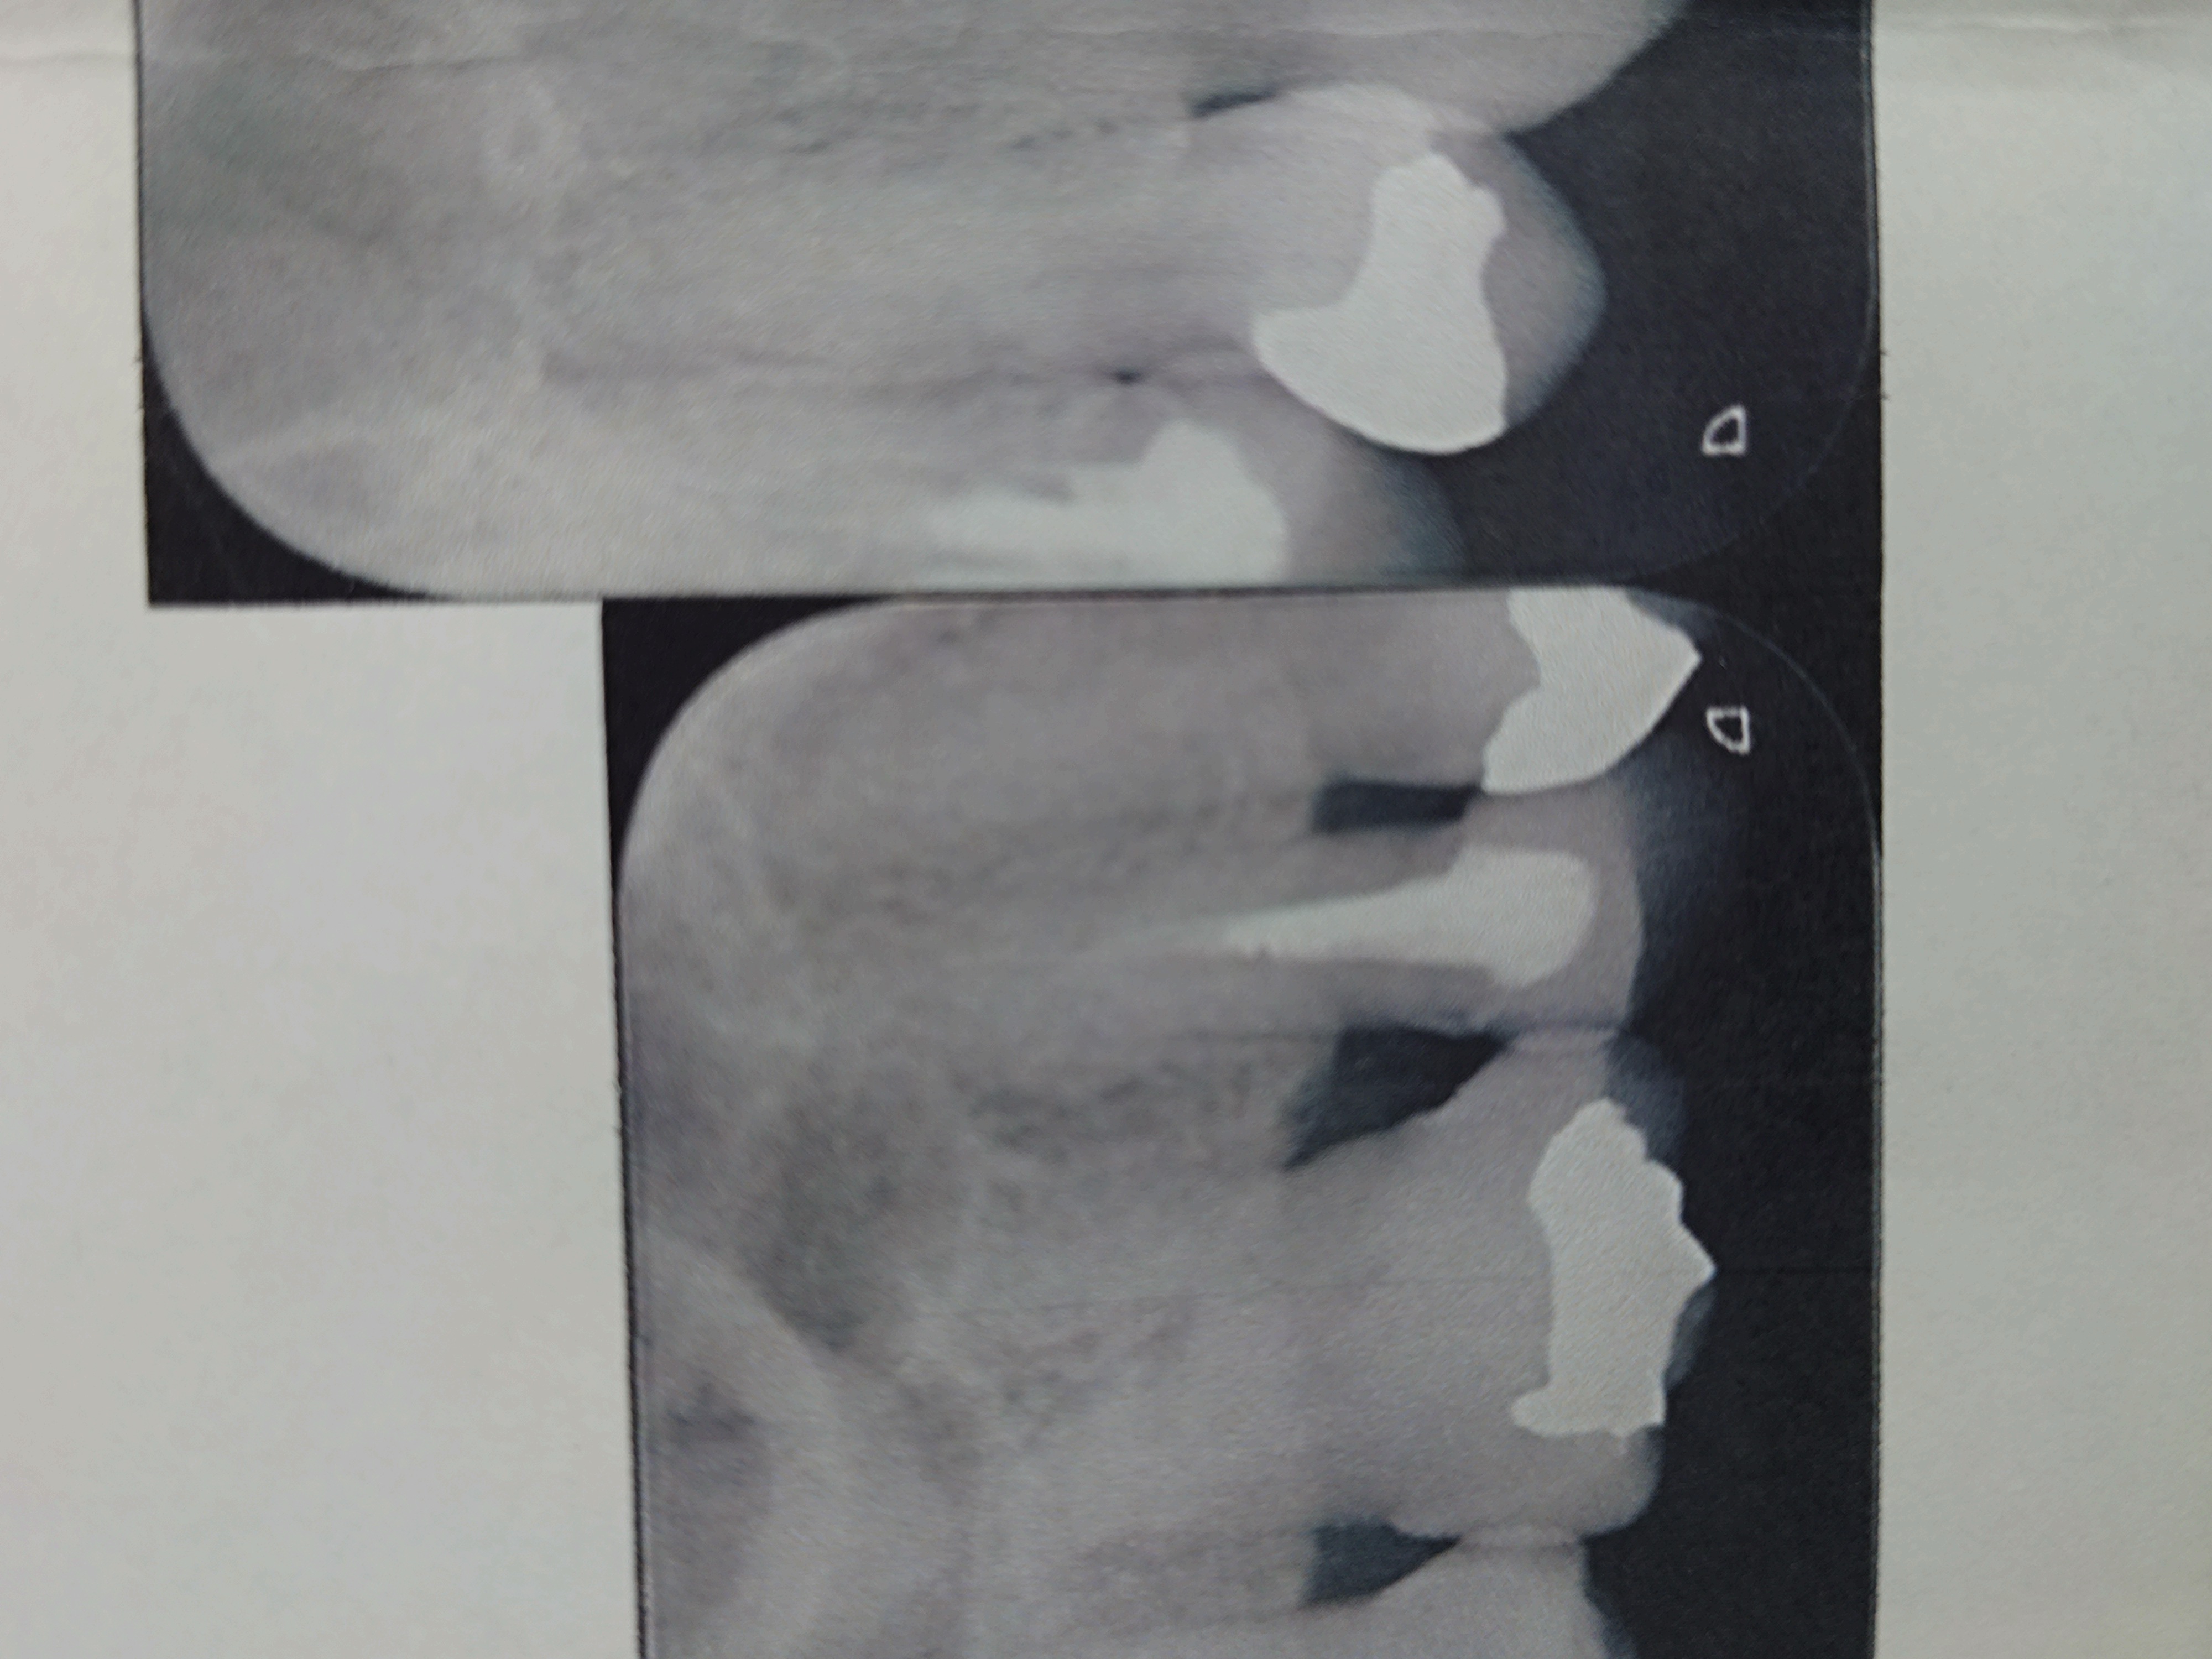

かかりつけ医院とは違うB歯科医院を受診し、レントゲンCTを撮りました。

15年ほど前に保険診療根管治療をしている歯なのですが、根管充填が不十分で半分ほどから根の先にかけて空洞でした。

そして、入っていたコアはスクリューピンでした。

スクリューピンもそこまで深いわけでもなく、除去するのにそれほどのリスクはなさそうに見えます。